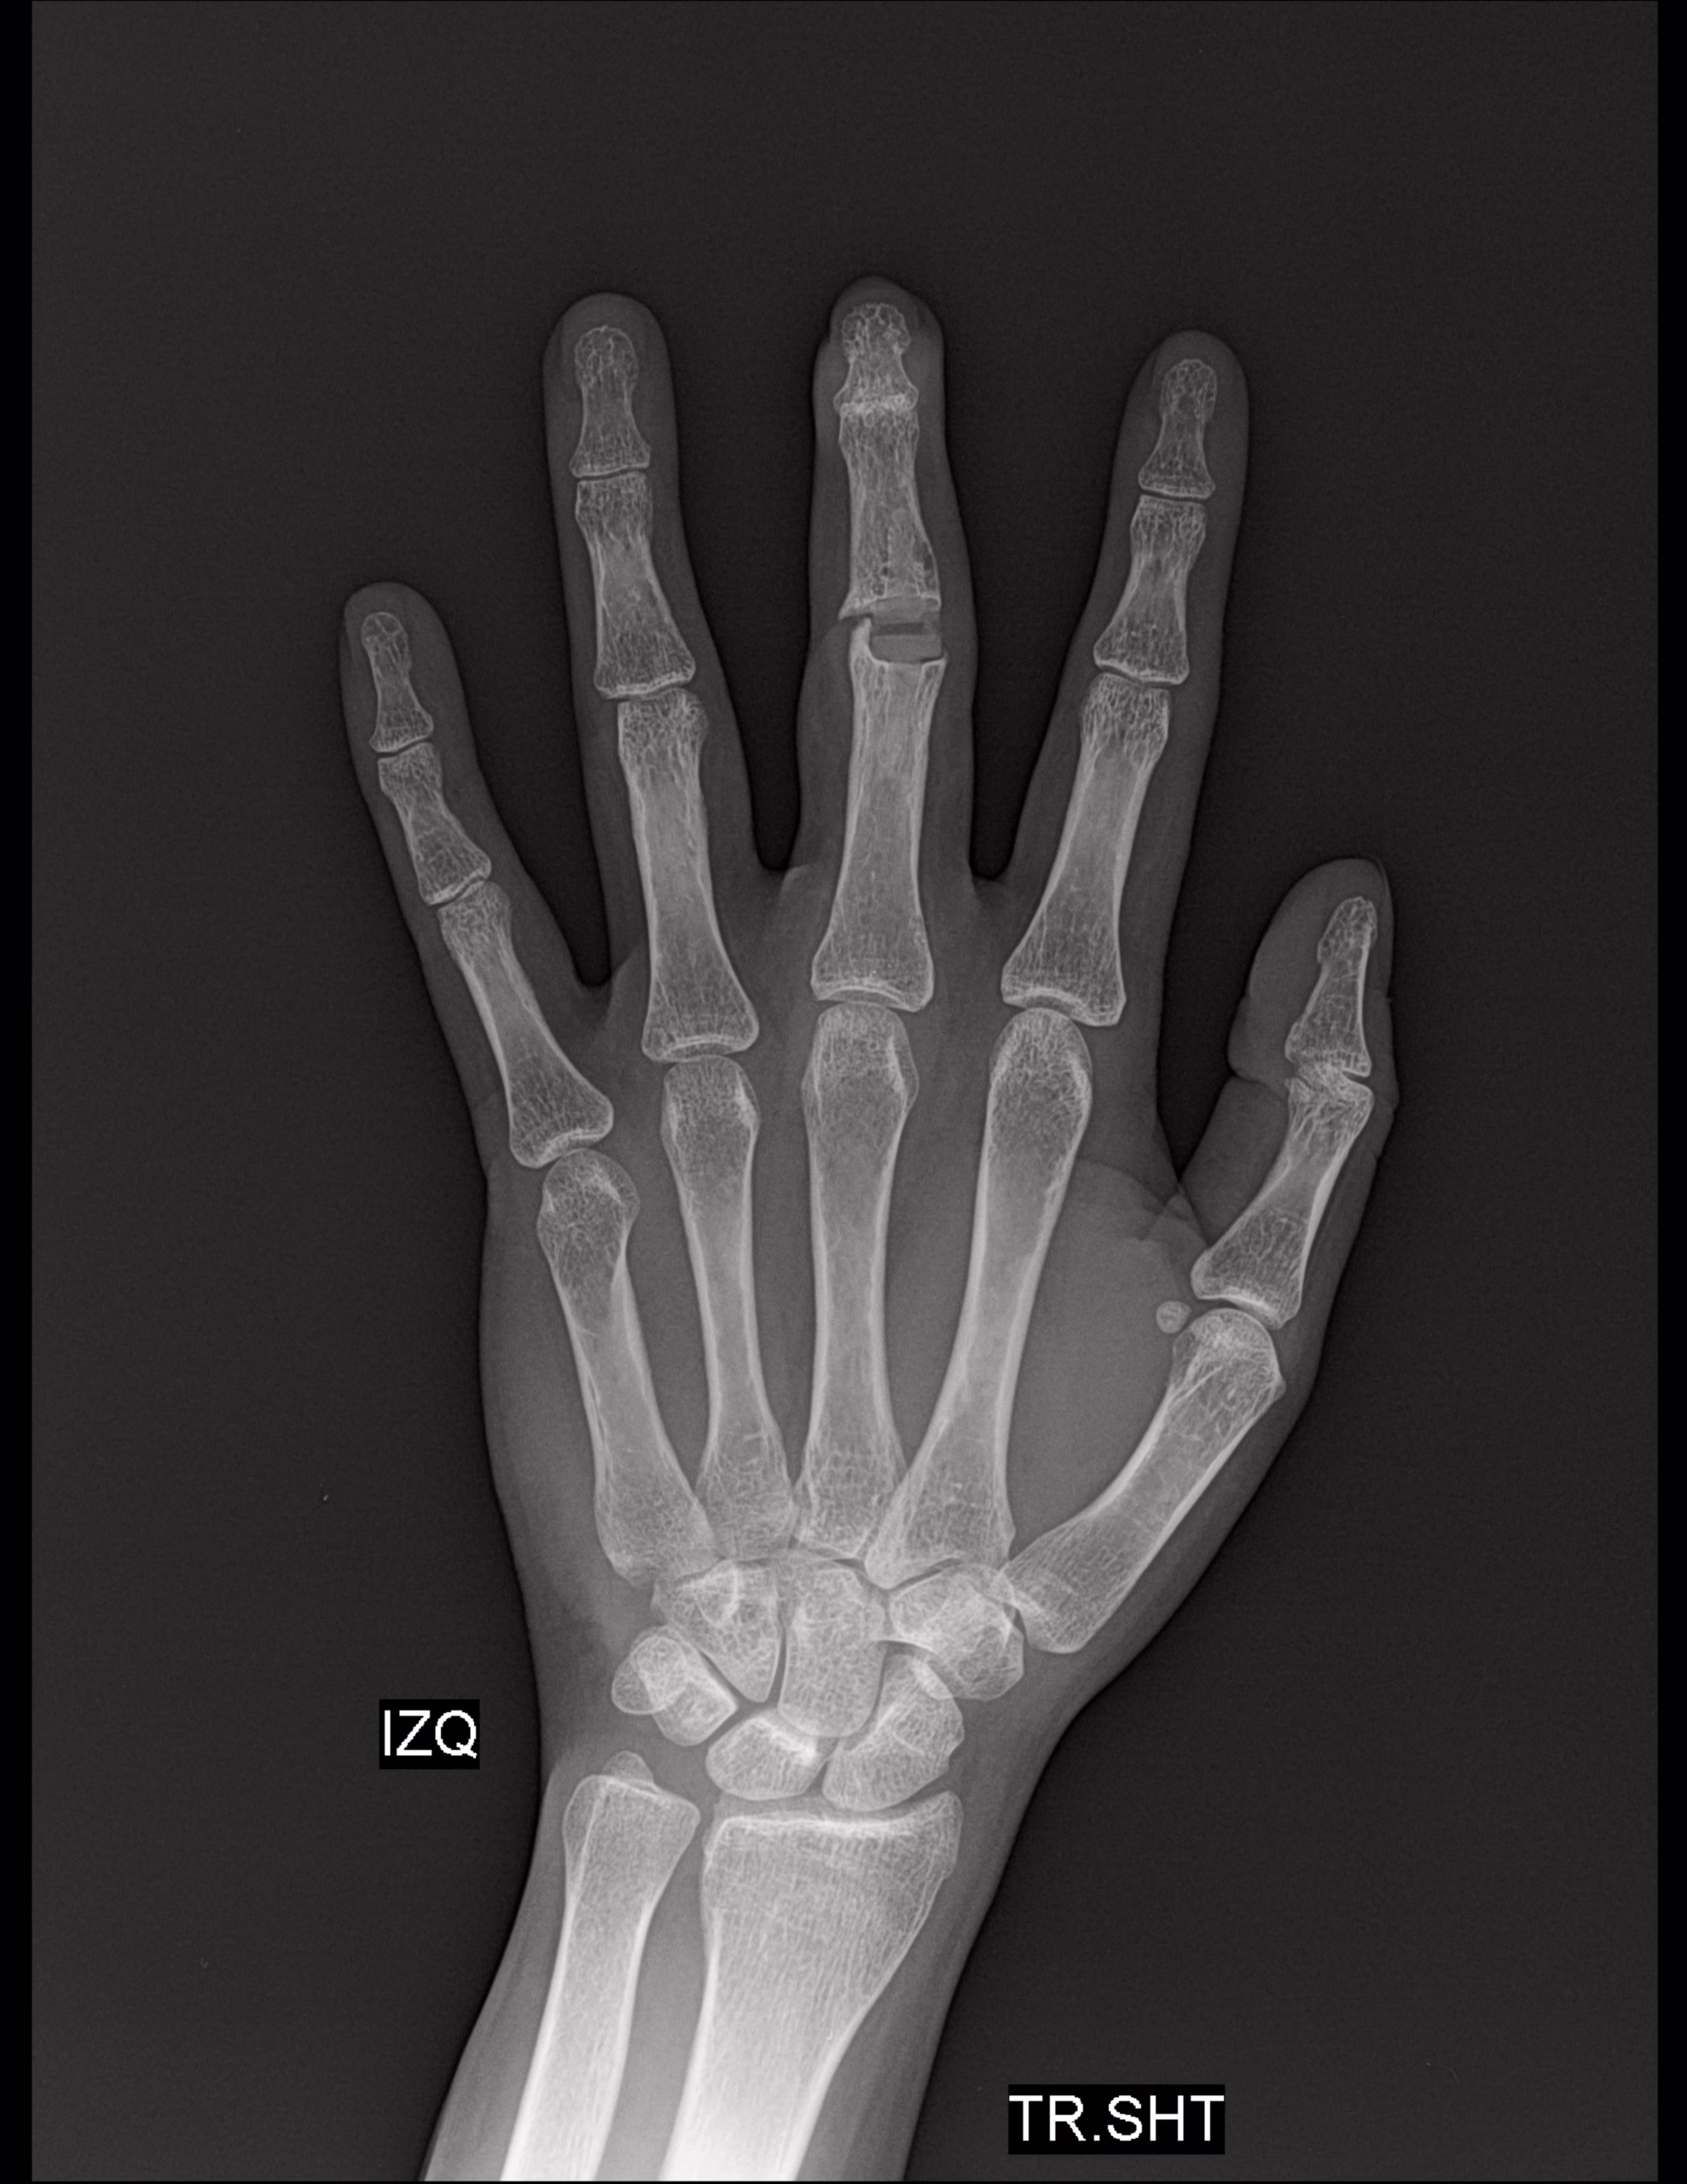

RADIOGRAFIAS AP Y LATERAL DE MANO

-Radio y cubito, con aumento la densidad y grosor a nivel interfalángico proximal de dedo medio. Resto sin evidencia de lesiones líticas, blásticas o perdidas de la contigüidad.

-A nivel de falange proximal de dedo medio a nivel de cabeza con presencia de material de artroplastia, así como también a nivel de base de falange media. Resto de huesos del carpo, metacarpos y falanges, sin evidencia de lesiones blásticas, líticas o perdidas de la contigüidad.

-Espacio articular interfalángico proximal de dedo medio con material de artroplastia y presencia de fragmentos. Resto de los espacios articulares sin alteraciones

-A nivel de primera articulación metacarpofalángica, con presencia de hueso sesamoideo.

-Tejidos blandos, con adecuada densidad y grosor, sin evidencia de lesiones.

-Varíanza cubital neutra.

EN EL PRESENTE ESTUDIO RADIOGRÁFICO, EXISTE MATERIAL DE ARTROPLASTIA A NIVEL DE ARTICULAR INTERFALÁNGICO PROXIMAL DE DEDO MEDIO, EL CUAL ENTRE ELLOS SE OBSERVA APARENTES FRAGMENTOS ÓSEOS Y EDEMA ASOCIADO.